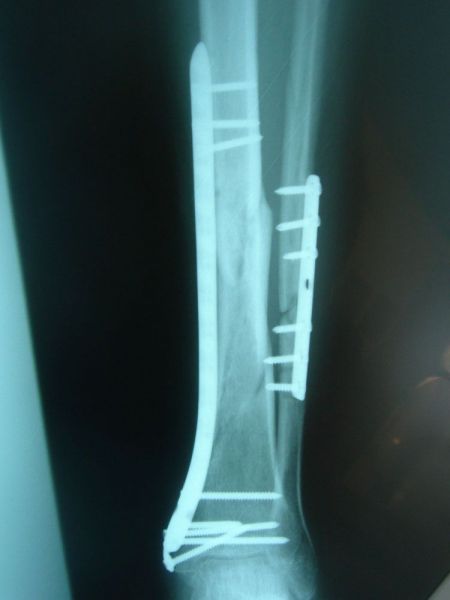

8 months post operation, process of healing in tibia and fibula